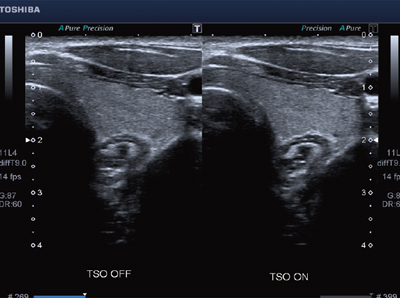

High Density Beamformingとは,高画質を実現する新画像エンジンである。生体特性(音速など)のバラツキによる方位分解能の劣化を補正し改善するTSO(Tissue Specific Optimization)(図2)をはじめ,空間/周波数コンパウンド技術により空間分解能を向上させるApliPure+や,組織の連続性を高め,コントラスト分解能を向上させるPrecision Imagingにより高画質を実現している。また,腹部エコーにおいて,従来の画質を保ちつつ従来の2倍以上のフレームレートを実現し,小病変の検出能の向上が期待される。

図2 TSOが働いている右の画像では方位分解能が向上している